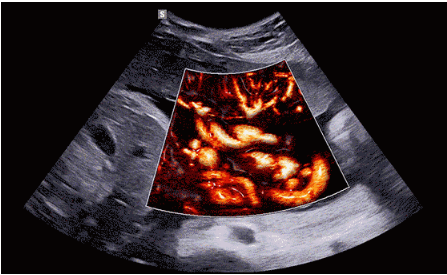

CrystalLive?是三星最新的超聲成像引擎,同時增強了2D圖像處理能力、3D渲染能力和彩色信號處理能力,能夠在復雜情況下提供出色的圖像性能,具備檢測外周血管、微循環(huán)血流的能力。

3D/4D成像方面,Hera i 10通過結合先進的圖像渲染技術,著重加強了邊緣和小結構的可視化能力。